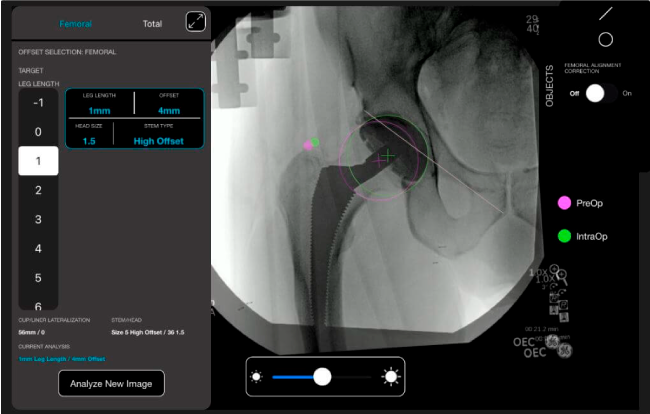

Navegador Velys Hip

cirugía de prótesis de cadera

Nuestro sistema de navegación digital VELYS HIP NAVIGATION ™ para cirugía de cadera, es una tecnología innovadora y no invasiva diseñada para apoyar la toma de decisiones de los médicos en tiempo real y basada en datos; aumentando la precisión y dando mejores resultados.

El sistema de navegación digital VELYS HIP NAVIGATION ™ para cirugía de cadera, es una tecnología innovadora y no invasiva diseñada para potencializar la toma de decisiones en tiempo real y basada en datos; aumentando la precisión y mejorando los resultados a corto, mediano y largo plazo para los pacientes.

Planeación preoperatoria mediante la creación de plantillas digitales para reemplazo de cadera y análisis intraoperatorio

• Aumenta la precisión y reproducibilidad quirúrgica generando resultados predecibles.

• Datos procesables en tiempo real para la toma de decisiones.

Mayor nivel de información intraoperatoria facilita la colocación correcta de los implantes:

• Inclinación y anteversión de la copa acetabular para una correcta colocación del implante.

• Desplazamiento y offset para posicionamiento óptimo del componente (vástago) femoral.

• Verificación de la posición deseada del implante que potencialmente puede ayudar a reducir la probabilidad de dislocación protésica y aumentar la estabilidad de la articulación.

• Anotaciones digitales y herramientas de análisis de longitud de pierna.

• Con tecnología ONETRIAL® que calcula automáticamente el cambio en la longitud de la pierna y el desplazamiento para todas las combinaciones de implantes en una tabla fácil de leer.